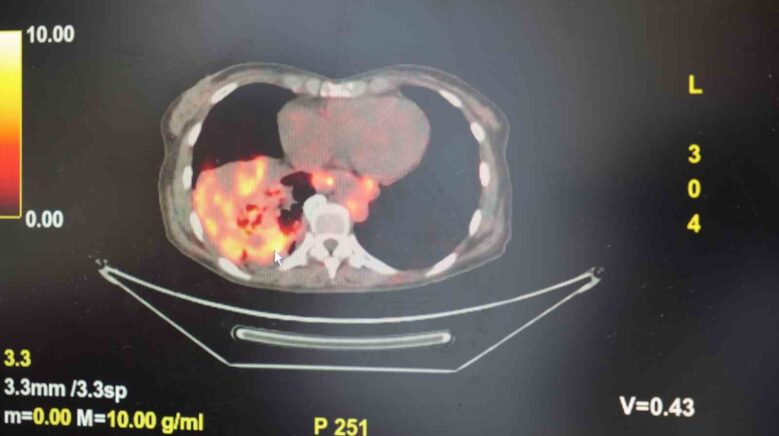

Dünyanın en itibarlı tıp mecmualarından yayımlanan bir araştırma üzerinde açıklama yapan Prof. Dr. Şevket Özkaya, araştırmaya nazaran, sigara içmeyenlerde en sık görülen cins olan akciğer adenokarsinomu, bayanlarda akciğer kanserlerinin yaklaşık yüzde 60’ını oluşturduğunu söyledi. Prof. Dr. Özkaya, sigara dışındaki risk faktörlerinin başında radon gazının geldiğine dikkat çekerek, “Radon gazı, konutlarımızda farkında olmadan soluduğumuz, renksiz, kokusuz, tatsız ve radyoaktif bir gazdır. Müsaade edilen pahaların üzerinde solunduğunda akciğer kanseri riskini artırıyor. Radon gazı bilhassa taş, toprak ve çimento üzere yapı gereçlerinde doğal olarak bulunuyor. Bu unsurlardan ortama daima yayılan gaz, teneffüs yoluyla akciğerlere ulaşıyor” tabirlerini kullandı.